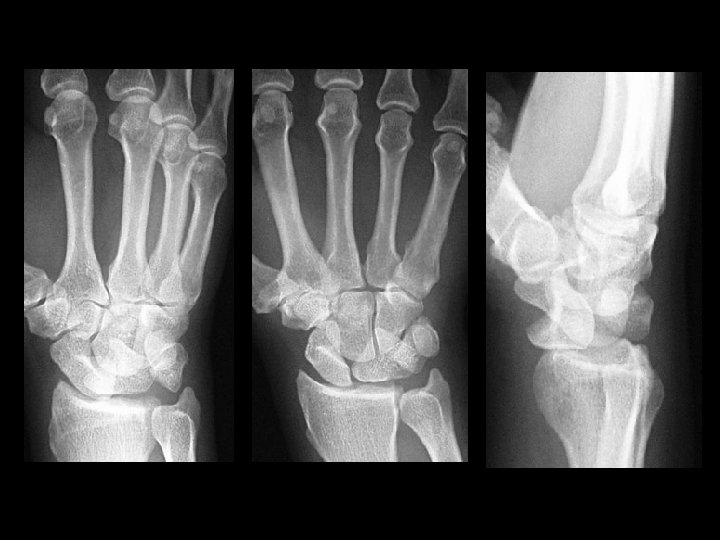

Trans-scaphoid perilunate dislocation • Findings: – Fracture of the radial styloid, scaphoid, and ulnar styloid – Posterior dislocation of the capitellum • ddx: – NONE! – This is an Aunt Minnie!

Lunate dislocation • Findings: – Disruption of proximal carpal row – “Pie-shaped lunate” – Lateral view is diagnostic • ddx: – NONE! – This is an Aunt Minnie!